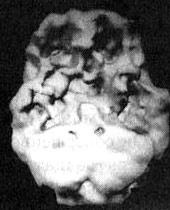

Мозг Дага. Последствия злоупотребления героином и метадоном

Трехмерное изображение поверхности, вид сверху. Обратите внимание на многочисленные «провалы» активности на всей поверхности мозга.